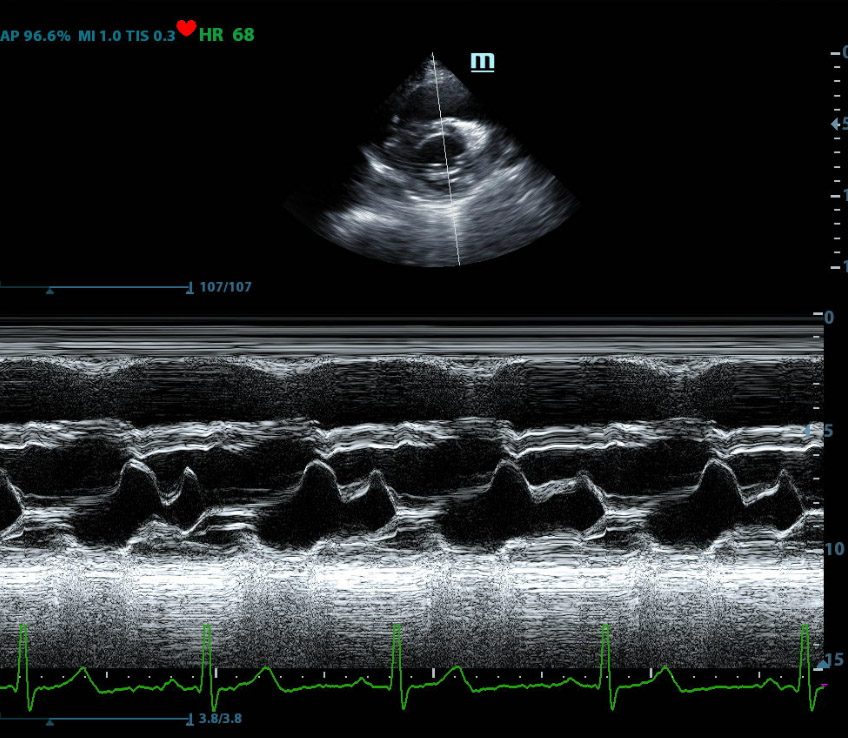

- Performing Diagnostic Ultrasounds: They use specialized equipment to direct high-frequency sound waves (ultrasound) into the patient’s cardiovascular system. These sound waves create images of the heart and blood vessels.

- Capturing and Analyzing Images: Sonographers operate the ultrasound machine to collect data from reflected sound waves, which are then turned into images of the heart’s structures, vessels, valves, and blood flow. They carefully position the equipment to obtain the best possible images for diagnosis.

- Assisting Physicians in Diagnosis: The images they capture are used by physicians to diagnose cardiovascular conditions such as heart disease, valve disorders, and other abnormalities. Sonographers may also provide initial assessments or measurements that help in diagnosis.